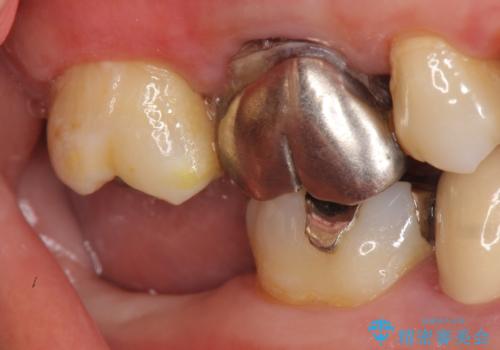

インプラントと骨の定着を待った後に二次手術を行い、カスタムアバットメント、オールセラミッククラウンによる補綴を行いました。

カスタムアバットメントは患者様それぞれの歯茎に合わせて製作されたオーダーメイドのアバットメントです。

既製のアバットメントに比べ適合がよく、高い清掃性を誇ります。